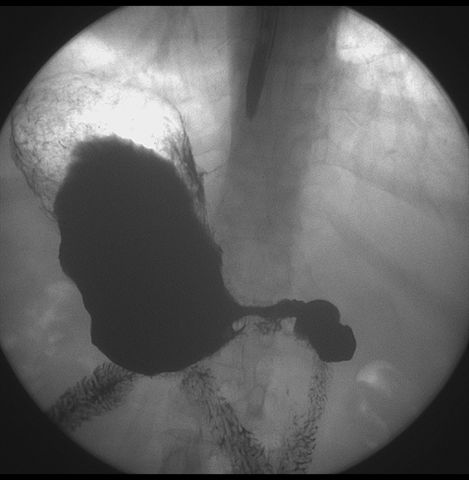

标题: X6872:F,69y,胃部不适。

胃窦至幽门段胃壁僵硬,扩张受限,局部纠集粘破坏,呈杵状。提示溃疡癌变可能性大。

胃窦癌可能性大,建议胃镜活检。钡剂太稀,吃的有点多。

支持考虑胃窦癌可能,胃内滞留液太多,胃窦部僵硬。

瀑布型胃,胃粘膜那是一个乱,窦部充盈不好,第16幅窦部粘膜反倒又很顺,先定个胃炎胃窦炎胃窦癌待排之类,建议进一步作胃镜检查。

胃窦部见钡池影,局部粘膜紊乱,纠集呈杵状改变,胃壁扩张受限,胃窦癌可能性大,建议胃镜检查.

胃窦部管腔扩张度较差,形态略有改变,胃窦粘膜显示欠佳,胃窦部占位可能性大,结合胃镜活检。

北京肿瘤医院胃镜诊断皮革胃。